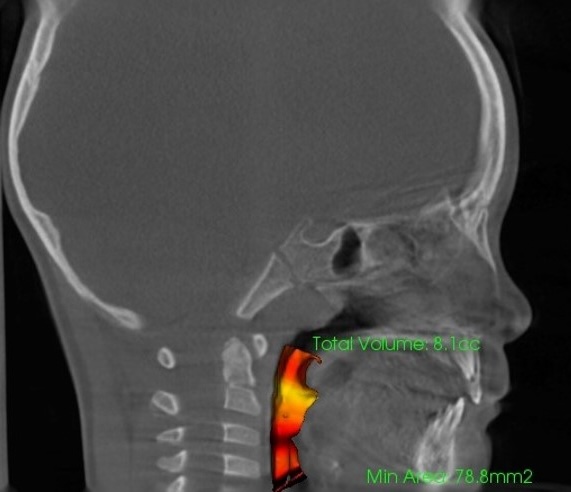

気道容積

鼻腔容積

- 診断根拠:CT等による鼻腔・気道・骨格等の画像及び数値解析

- 評価指標:気道容積・鼻腔容積の数値変化、骨格変化の数値解析、舌骨の位置や姿勢の改善評価等